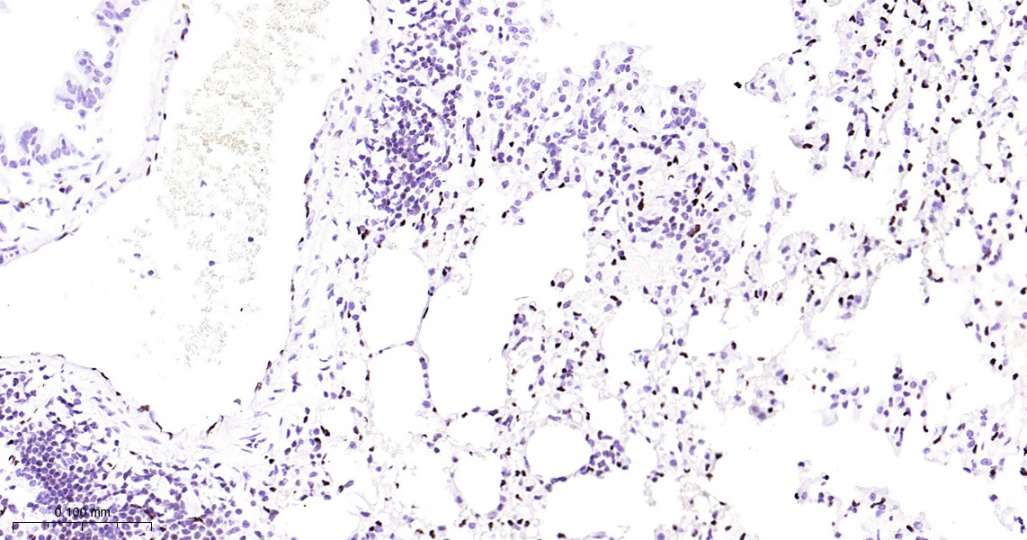

Immunohistochemical analysis of paraffin embedded Mouse lung tissue slide using IHC0529M (Mouse ERG Kit).